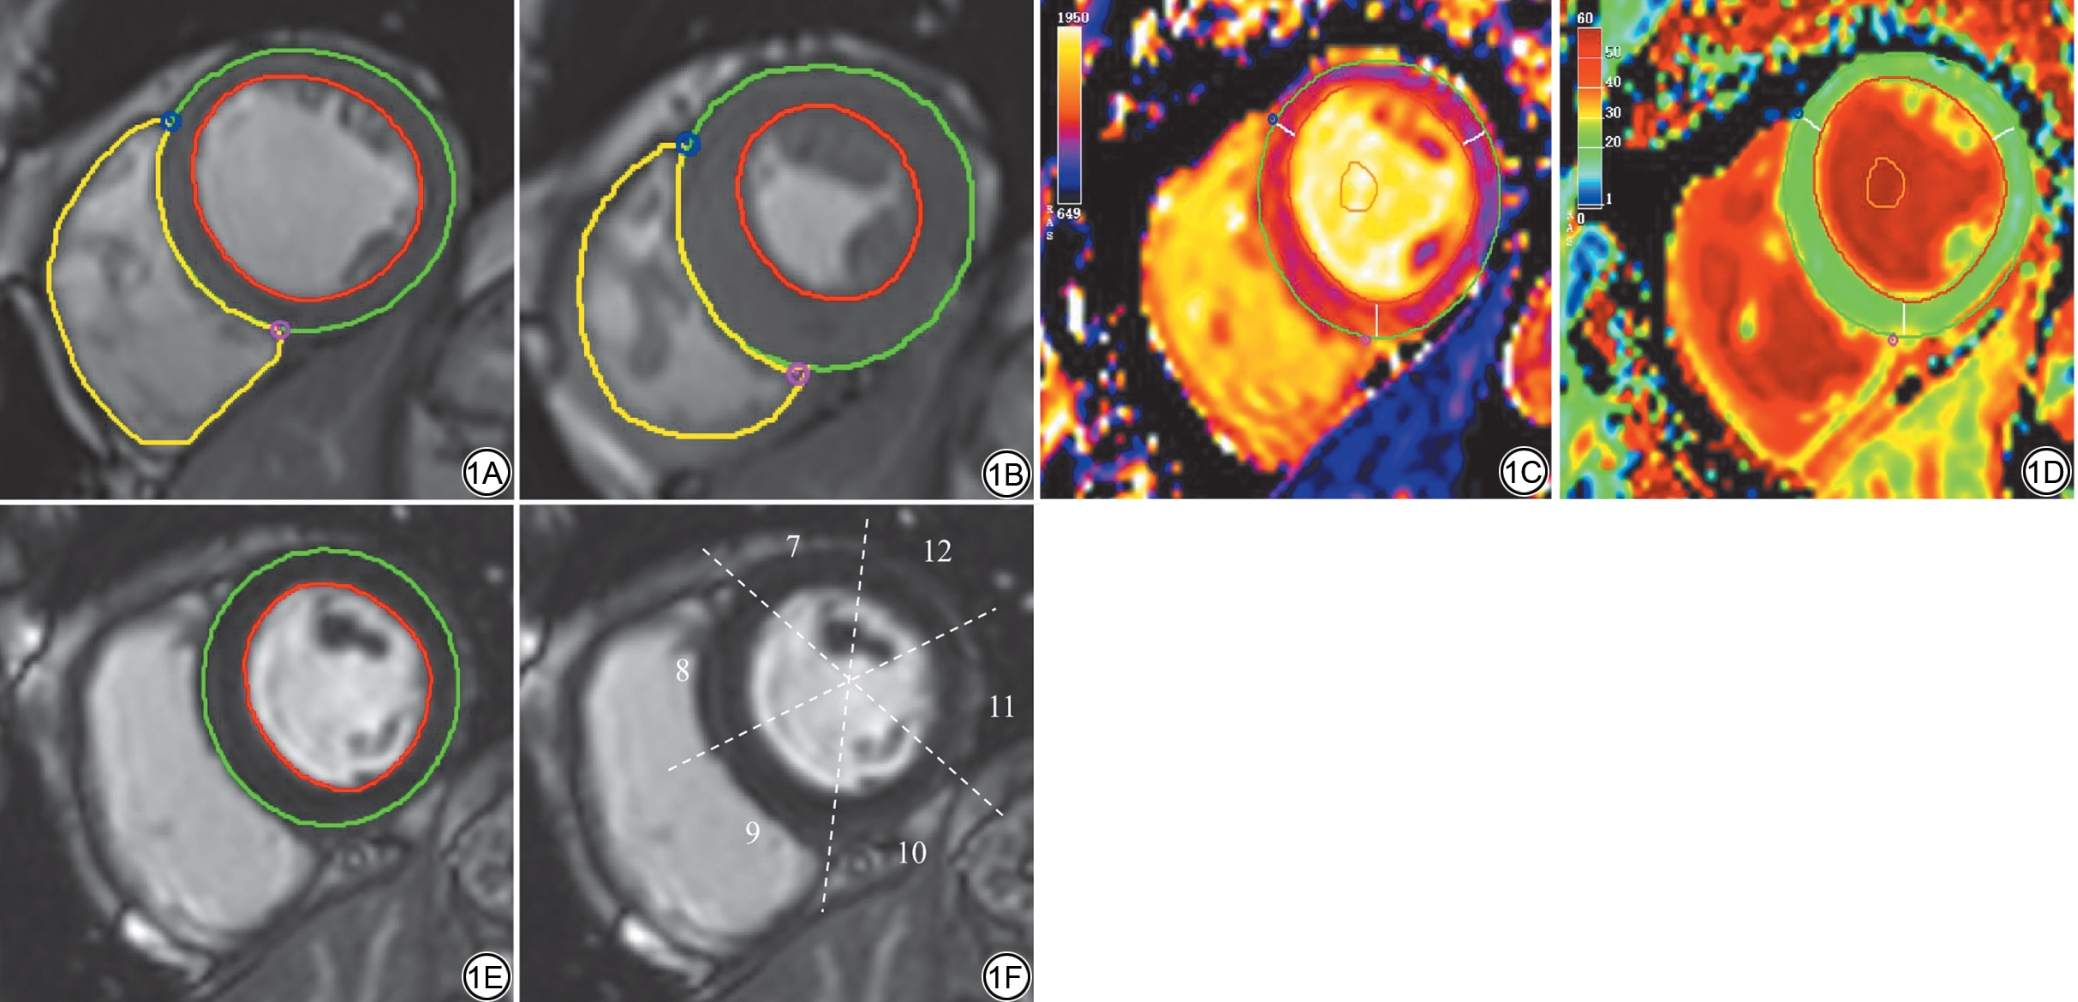

将CMR图像导出到图像后处理软件(CVI42, Circle Cardiovascular Imaging, Calgary, Canada),由两名放射科住院医师(分别具有6年和2年心血管影像诊断经验)独立评估,对受试者分组信息盲法。在舒张末期和收缩末期的短轴电影图像上半自动勾画左心室心内外膜轮廓和右心室心内膜轮廓,以评估双心室形态及功能学参数,并使用Mosteller公式计算的体表面积(body surface area, BSA),校正后用于统计学分析(图1A~1B)。左心室(left ventricular, LV)及右心室(right ventricular, RV)形态及功能学参数包括:心率(heart rate, HR)、射血分数(ejection fraction, EF)、舒张末期容积指数 (end diastolic volume index, EDVI)、收缩末期容积指数(end systolic volume index, ESVI)、每搏输出量指数(stroke volume index, SVI)、心脏指数(cardiac index, CI)、左心室心肌质量指数(left ventricular mass index, LVMI)。

心肌组织特征学参数包括:心肌整体初始T1(native T1)值、T2值和细胞外容积分数(extracellular volume, ECV),均为从基底部到心尖部三层短轴切面获取的平均值,测量时尽量避开乳头肌或血池伪影(图1C~1D)。ECV计算公式见式(1)[19]

在LGE图像上手动勾画左室短轴图像心外膜和心内膜(图1E),LGE阳性定义为病灶区信号强度超过同层面远隔正常心肌参考感兴趣区(region of interest, ROI)的均值+5个标准差(standard deviation, SD),并根据左心室质量计算LGE负荷(LGE%)[20, 21]。LGE按解剖定位分为左室前壁、侧壁、下壁、室间隔和插入部,按分布模式分为心内膜下和非心内膜下[22, 23]。根据美国心脏协会(American Heart Association, AHA)左室心肌16节段(不含心尖)划分法计算各节段LGE阳性率(图1F[24]

图1  心中部短轴位图像分析示意图。1A~1B:在舒张末期和收缩末期的电影图像勾画左心室心内外膜和右心室心内膜轮廓;1C~1D:在T1 mapping、ECV图像勾画左心室心内外膜和血池轮廓;1E:在LGE 图像勾画左心室心内外膜轮廓;1F:LGE 图像上左室心肌16 节段中第7~12 节段划分示意图。ECV:细胞外容积;LGE:延迟强化。

Fig. 1  Schematic diagram of image analysis for the mid-ventricular short-axis view. 1A to 1B: Endocardial and epicardial contours of the LV and the endocardial contour of the RV are drawn on cine images in end-diastole and end-systole phases. 1C to 1D: LV endocardial and epicardial contours along with the blood pool region are drawn on T1 mapping and ECV images. 1E: LV endocardial and epicardial contours are drawn on the LGE image. 1F: Schematic representation of segment division (segments 7 to 12) within the 16 segments of LV on LGE images. LV: left ventricle; RV: right ventricle; ECV: extracellular volume; LGE: late gadolinium enhancement.